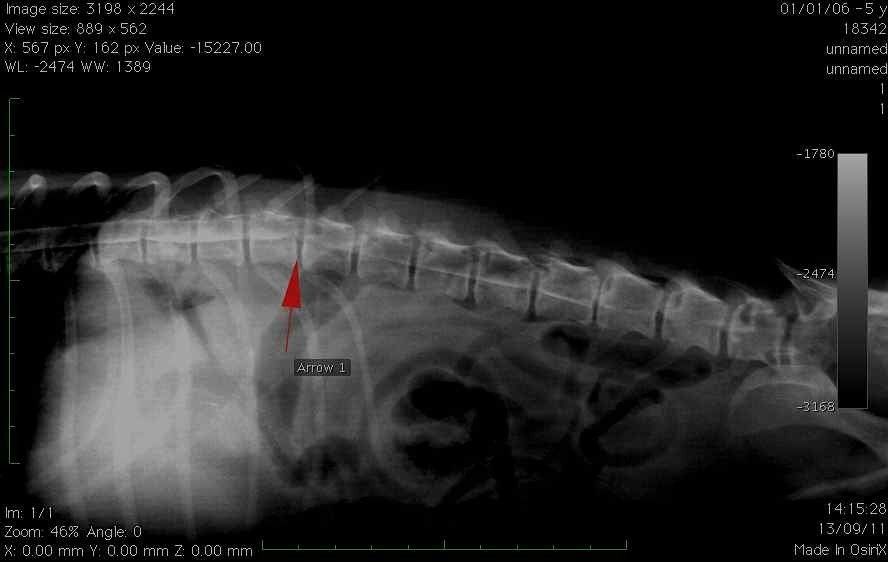

Notre unité chirurgicale pratique également des interventions de chirurgie vertébrale:

- Les chirurgies de hernie discale qui sont devenues les premières pathologies rencontrées en neurologie chez le chien.